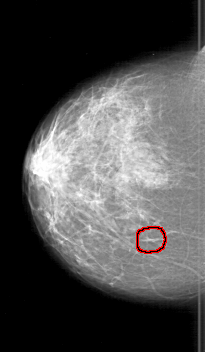

D_4197_1.LEFT_MLO

LEFT_MLO LINES 5116 PIXELS_PER_LINE 3841 BITS_PER_PIXEL 12 RESOLUTION 43.5 NON_OVERLAY

FILE: D_4197_1.RIGHT_CC.OVERLAY

TOTAL_ABNORMALITIES 1

ABNORMALITY 1

LESION_TYPE CALCIFICATION TYPE PUNCTATE DISTRIBUTION CLUSTERED

ASSESSMENT 0

SUBTLETY 2

PATHOLOGY BENIGN

TOTAL_OUTLINES 1

BOUNDARY